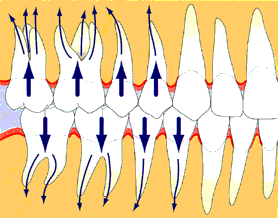

歯周炎の進行

歯周炎の進行は短時間に急速に歯周組織の破壊が進行する活動期と長期間にわたり破壊の進行しない非活動期(静止期)が間歇的に繰り返されます。

咬み合わせが悪いと歯周病が悪化します

正常な噛み合わせであれば、ものを噛む力(咬合力)を均等に分散し、歯への負担を極力軽減します。

もし噛み合わせが悪いと、一部の歯に力が集中し、それらの歯を支える歯槽骨や歯周組織を破壊してしまいます。